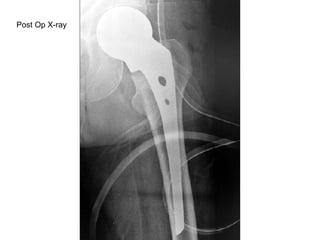

Post Op X-ray

Selection of Implant Pre operative planning Intra-operative planning Correct head diameter Correct stem width Correct length of collar Cement Tension band wiring

Prosthesis design: Proper Offset Stem Diameter Neck over hang Fitness at proximal part